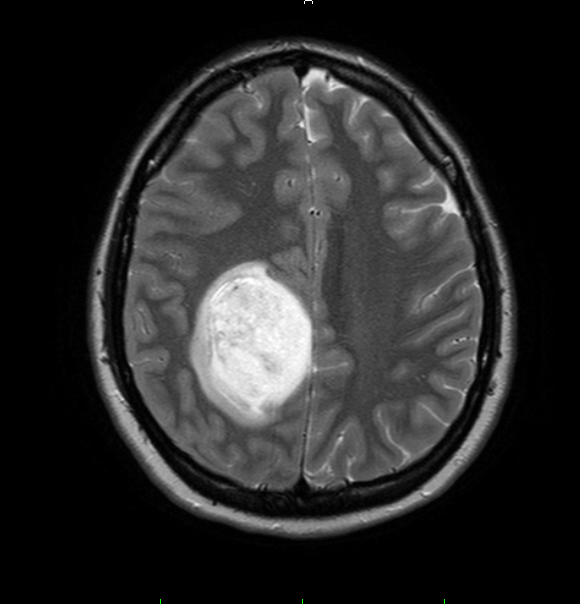

In varsta de 34 de ani, Oana a fost diagnosticata cu o tumora pe creier, fiind operata la Spitalul Bagdasar, in 2010, urmand apoi un tratament cu radioterapie.

Insa, in urma cu doua luni, boala a revenit - mai agresiva ca niciodata. Tanara nu mai poate fi operata in Romania, pentru ca nu mai are o tumora compacta, ci o gramada de celule foarte agresive, raspandite și infiltrate printre cele sanatoase. Dar exista in Canada, la Montreal Neurological Institute and Hospital, posibilitatea unei operații printr-o tehnica speciala. Se numește fluorescence-guided resection of brain tumors si presupune rezecția tumorii cu ajutorul unei substanțe fluorescente care delimiteaza vizual zonele infiltrate.